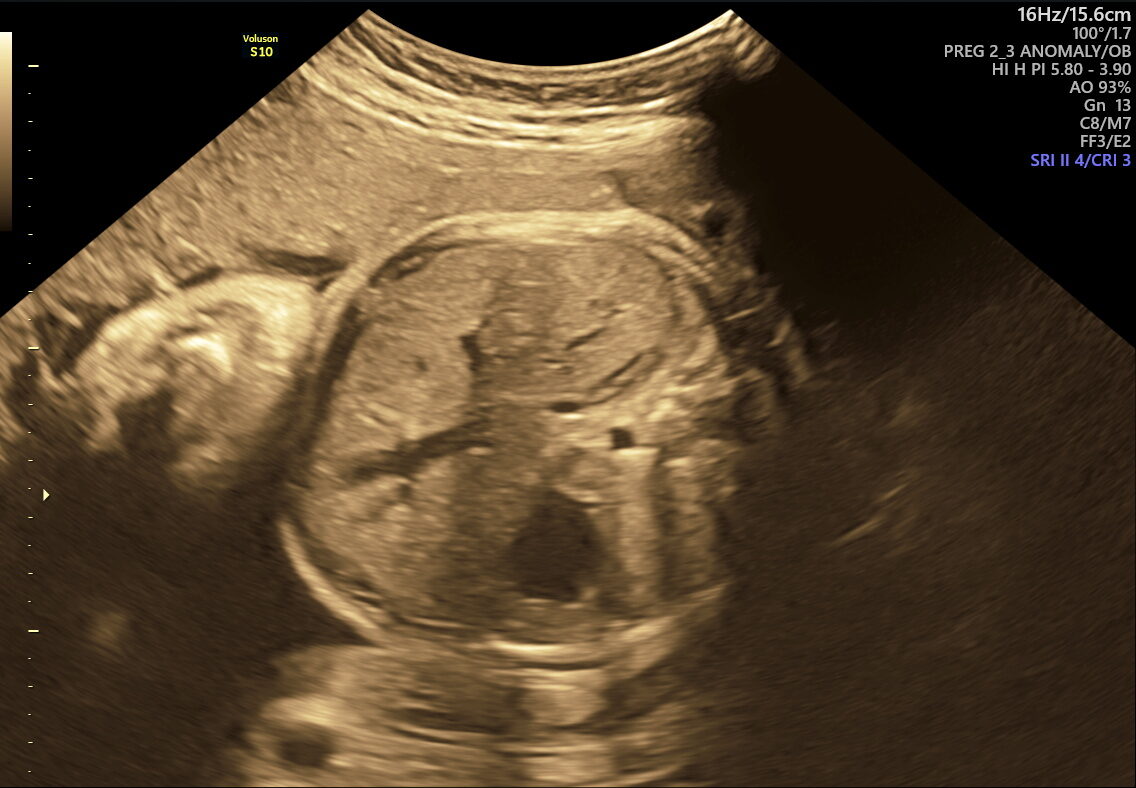

As your pregnancy journey enters its final weeks, NESA Institute of Fetal Medicine offers the Fetal Well-being Scan—a specialized ultrasound performed between 28 and 40 weeks. This essential check ensures your baby’s health and readiness for birth, giving you and your family confidence and clarity as you approach delivery.

This scan is designed to assess multiple aspects of your baby’s well-being and the mother’s preparedness for labour. Here’s what it covers:

- Birth Preparation: Confirms the baby’s position (head-down, breech, transverse) and checks readiness for labour.

This scan focuses on confirming birth readiness and spotting sudden issues that may arise close to your due date. It includes detailed Doppler studies to check blood flow in the umbilical cord and brain, ensuring your baby gets enough oxygen and nutrients.